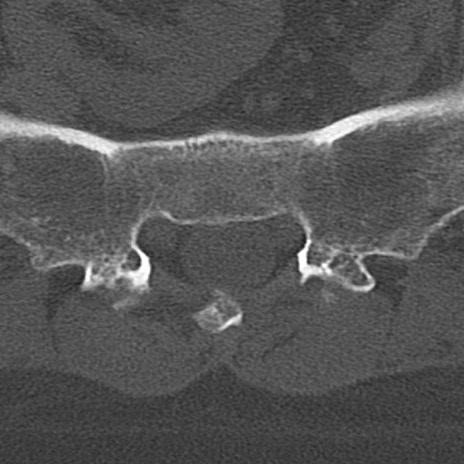

【整形】TIPS症例4 腰椎CT(横断像)

腰椎CT

横断像と矢状断像